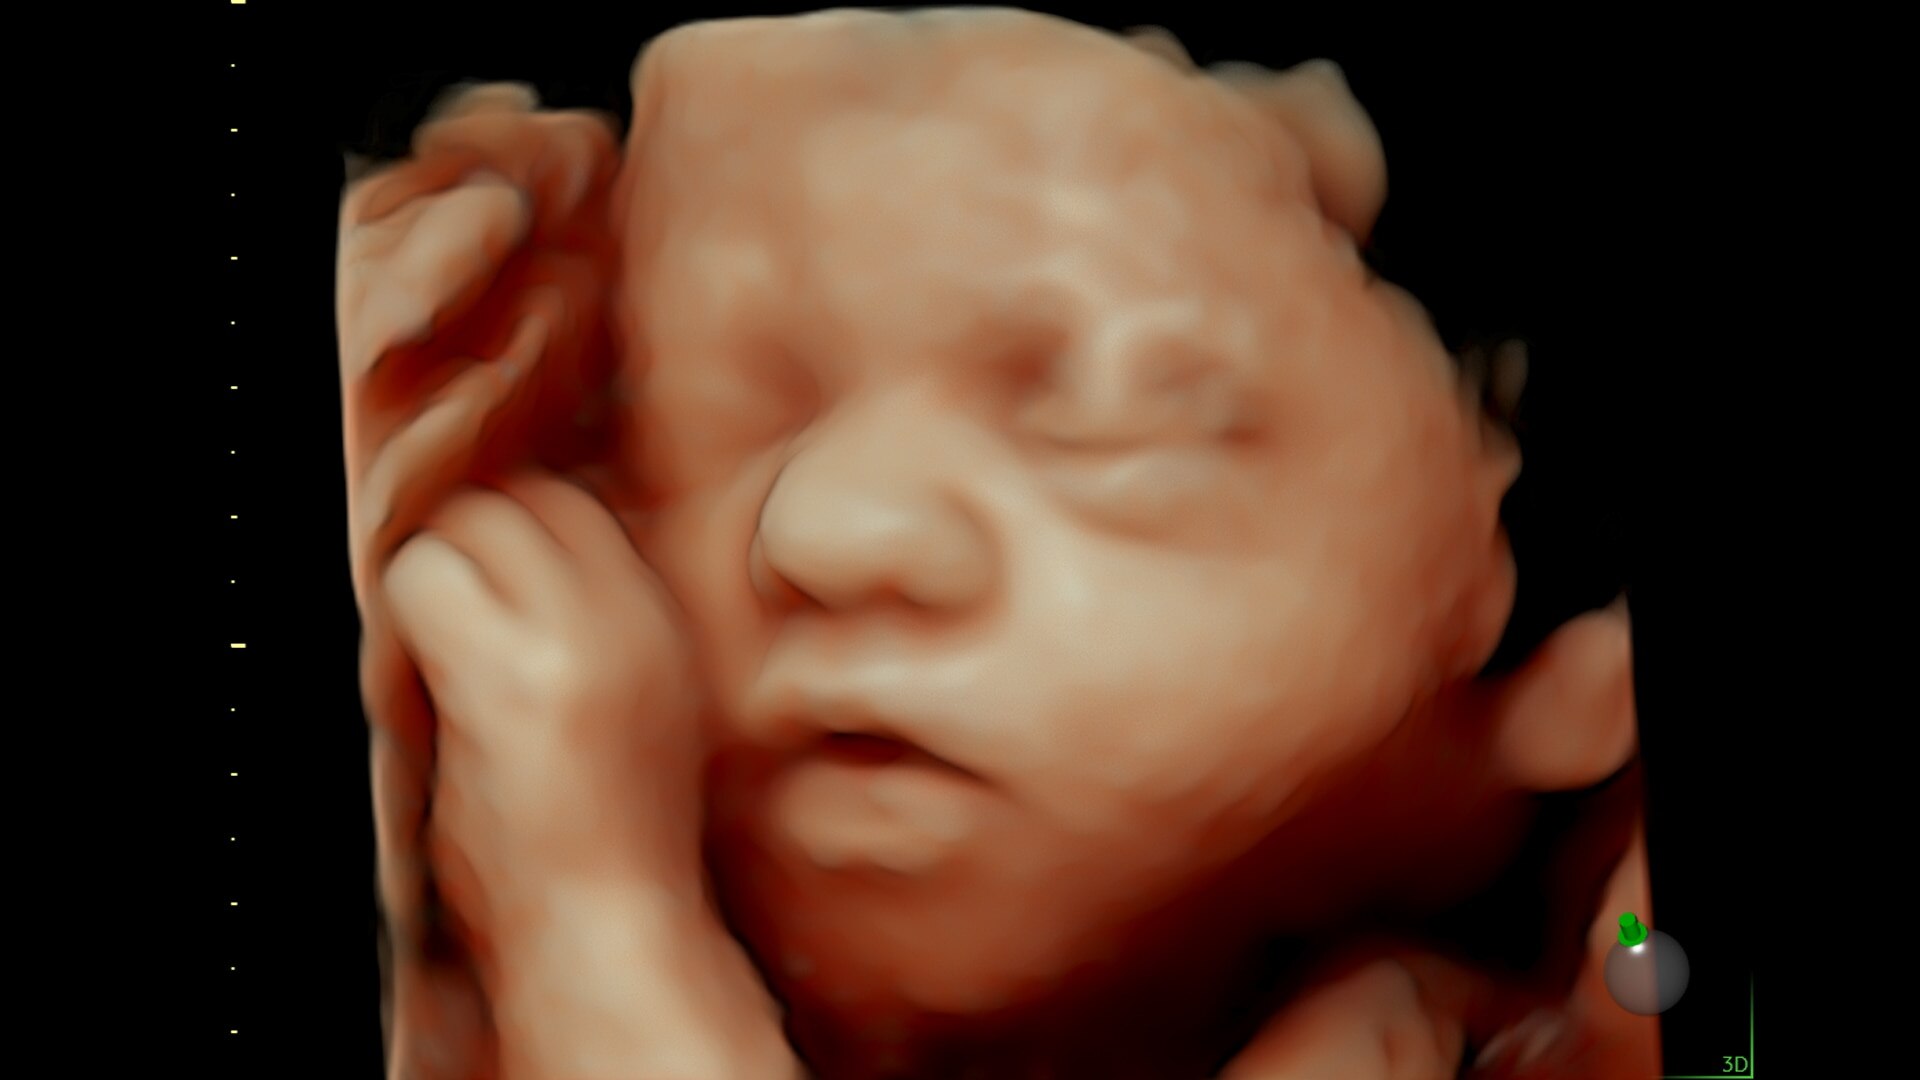

Advanced beamforming capabilities work in harmony with expert-level probes to deliver faster processing speeds and frame rates for enhanced detail and contrast resolution, greater color quality and sensitivity, and exceptional 3D/4D.

Fast, easy 3D-like blood flow visualization